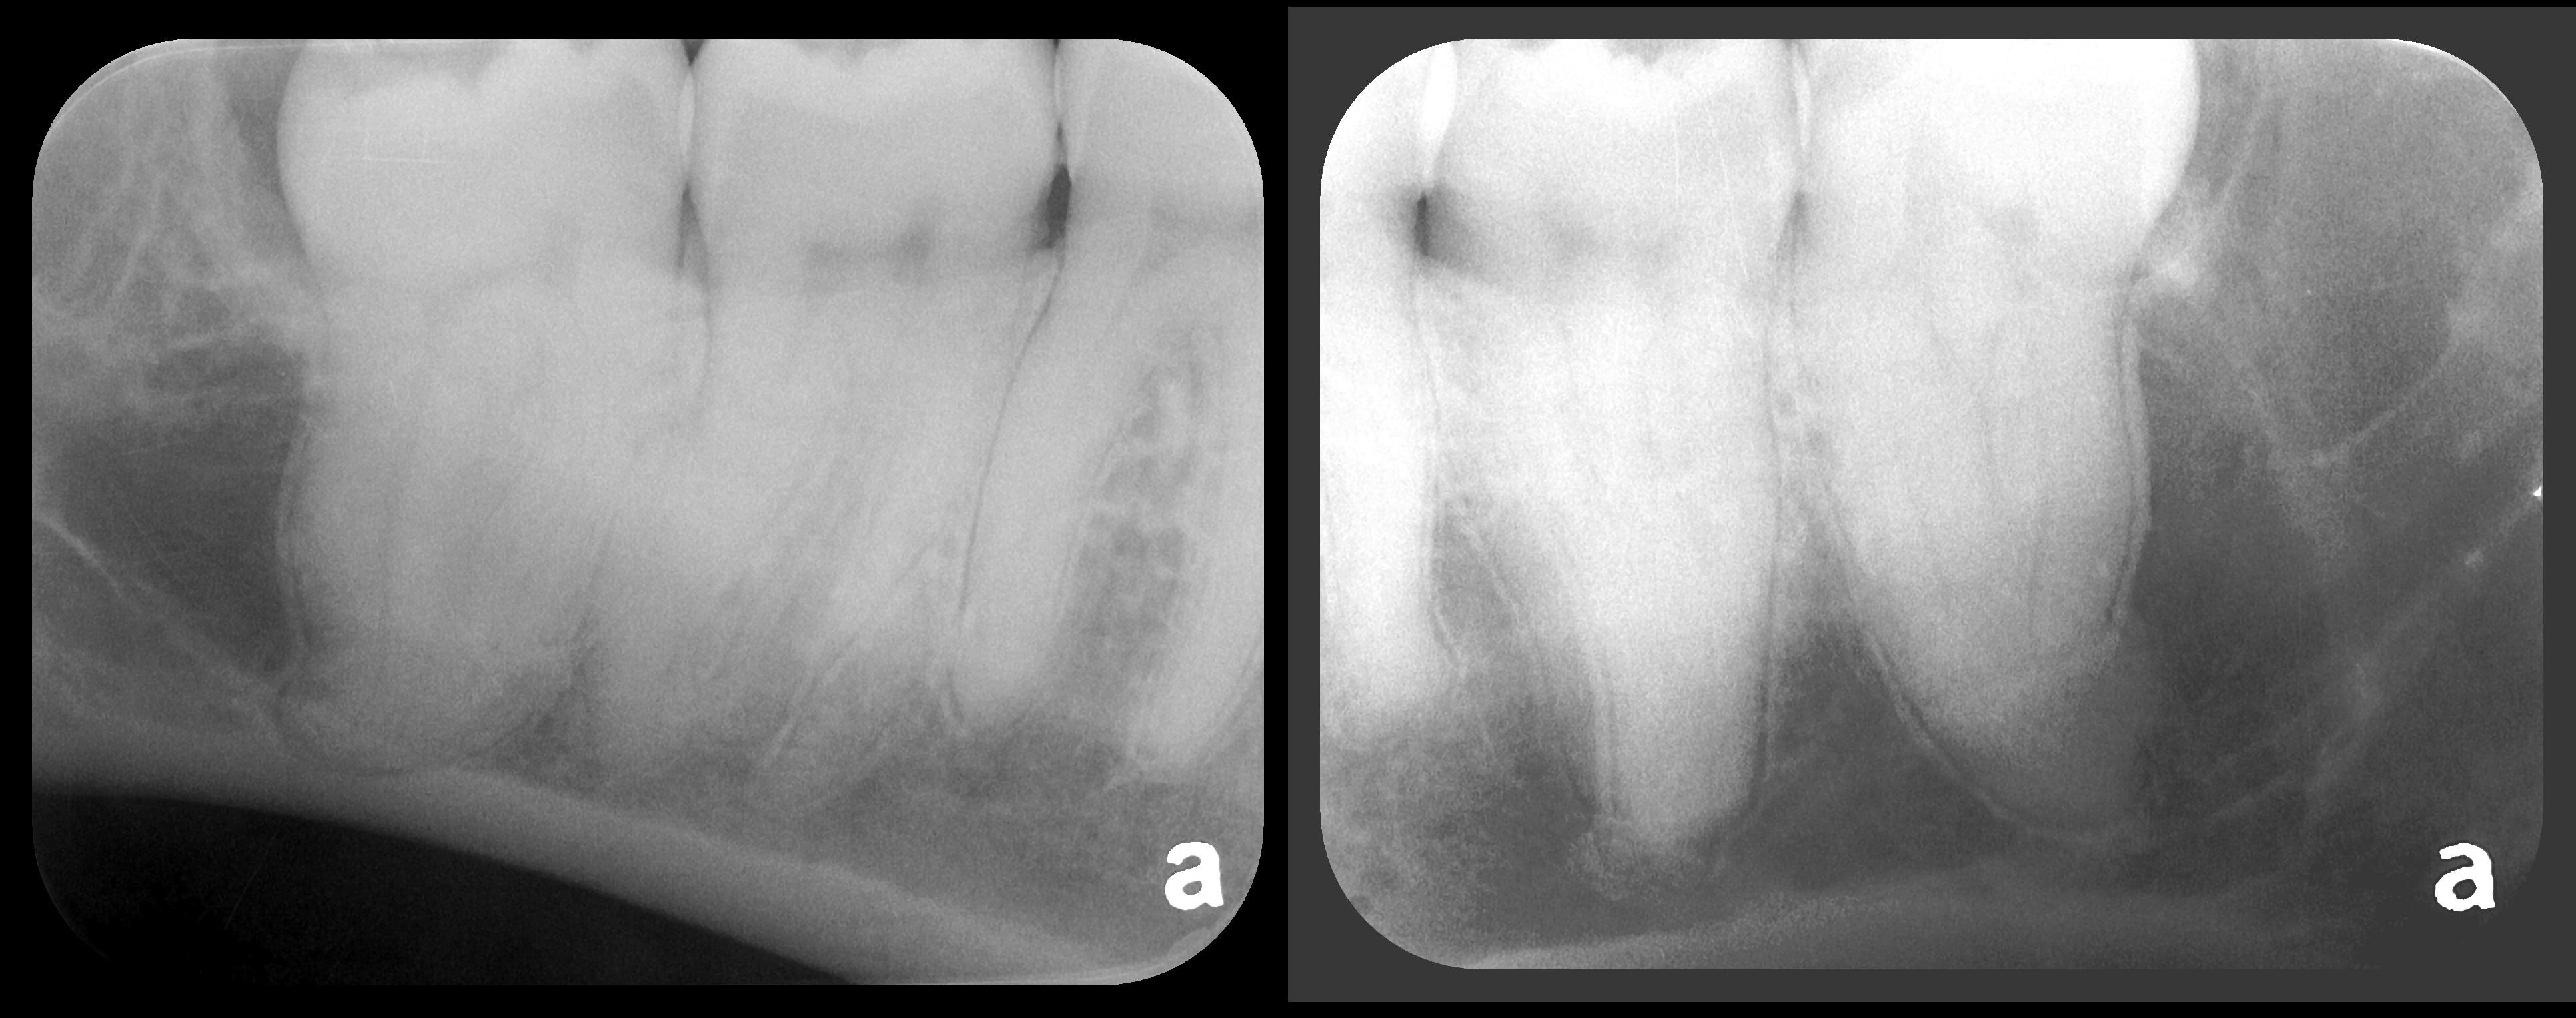

Fig 5. Bilateral concerns for this patient are evident on these PSP

radiographs. Tooth No. 17 may exhibit pathology distal to the root. In

addition, extreme length of root of tooth No. 32 through the entire height

of the body of the mandible is cause for concern if extractions of Nos.

17 and 32 are planned. Three-dimensional CBCT study and alerts to

the patient as to the potential surgical complications on extractions are

required in this instance. There is no benefit to panoramic radiography

in this case.

Figure 5

Fig 6. PA radiograph showing 90-degree dilacerations of

mesial and distal roots of tooth No. 32 and intersection of mandibular

canal with these roots. Extraction of tooth No. 32 requires 3D study, and

patient was advised as to this necessity.